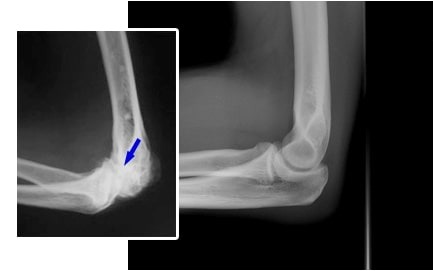

Liječenje zglobova lakta. Žena. 31 godina. Trajanje liječenja: 2 mjeseca. Hrskvica se potpuno oporavila: